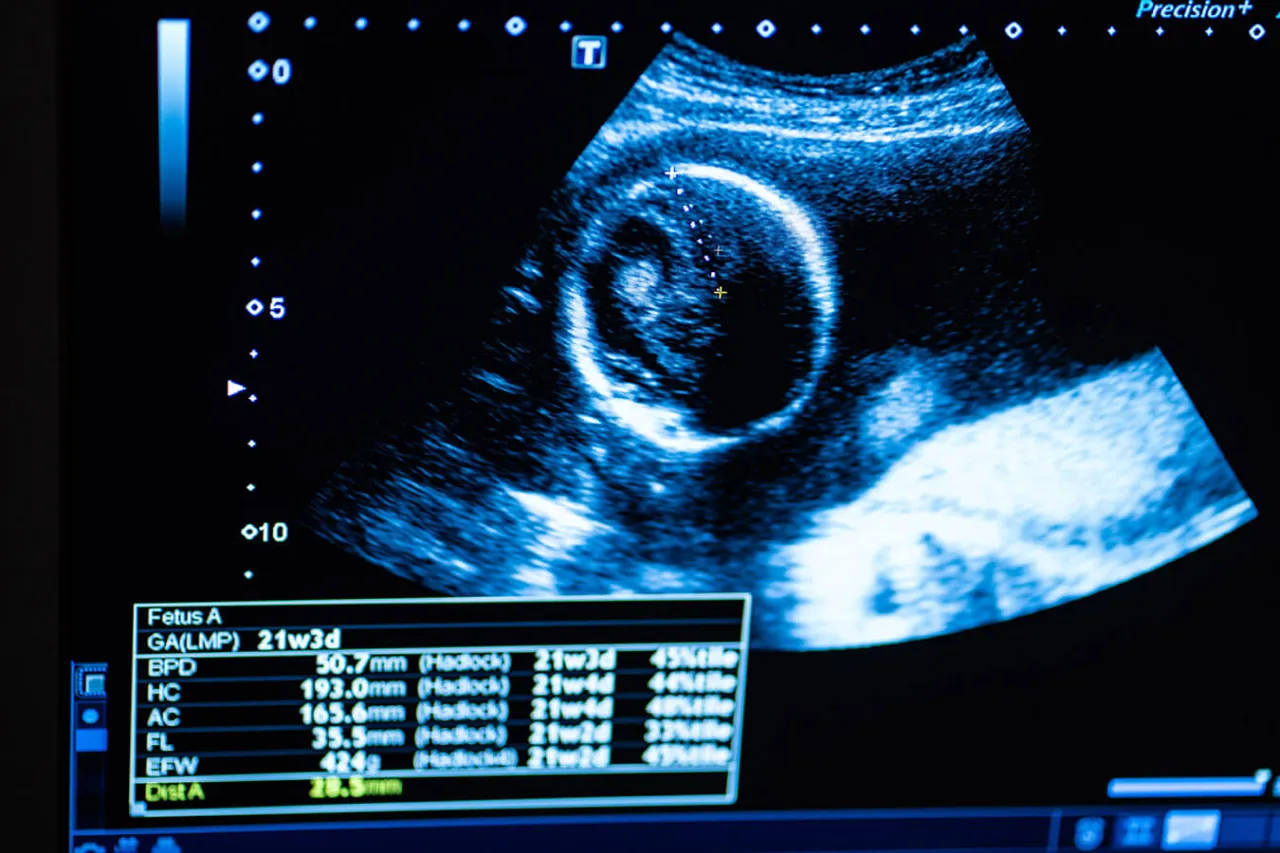

- Leczenie obejmuje farmakoterapię (kwas ursodeoksycholowy) i regularne monitorowanie stanu płodu (KTG, USG).

Aby zminimalizować to ryzyko, kluczowa jest regularna i ścisła kontrola stanu płodu. Obejmuje to częste badania KTG (kardiotokografia), które oceniają czynność serca dziecka i aktywność skurczową macicy, oraz badania USG z oceną przepływów w naczyniach płodu. Dzięki temu lekarz może na bieżąco monitorować samopoczucie maluszka i w razie potrzeby podjąć decyzję o wcześniejszym zakończeniu ciąży.